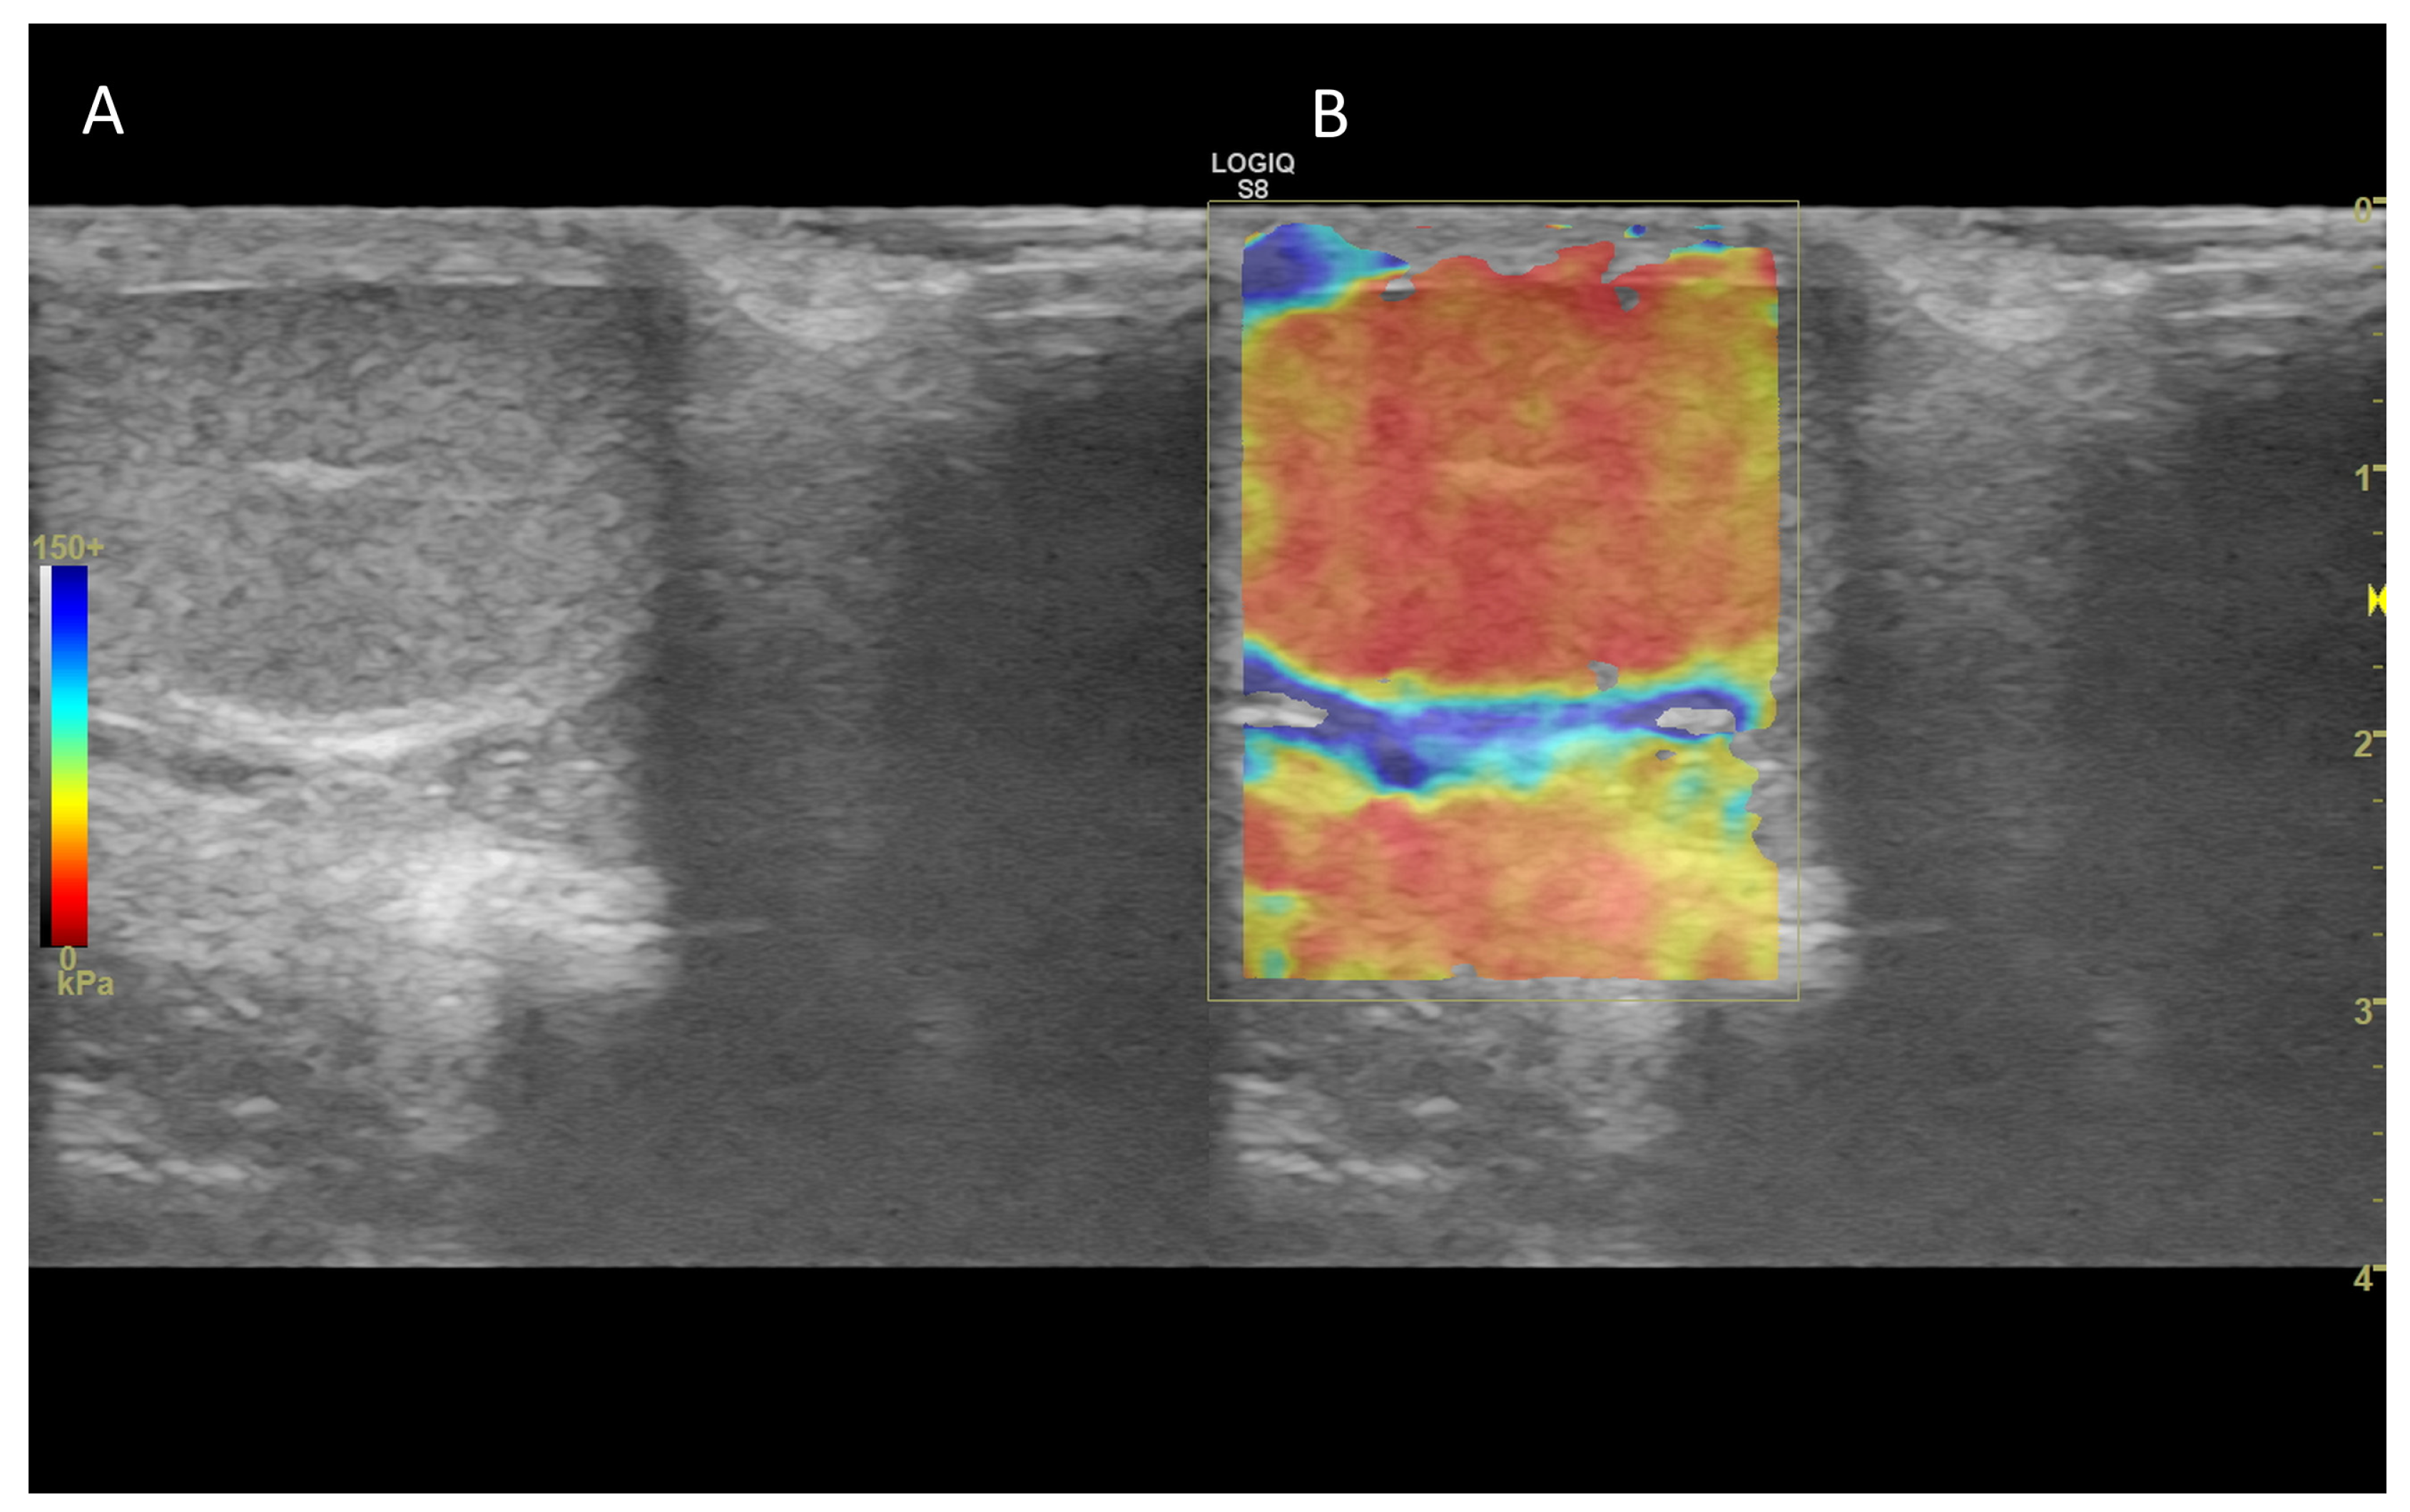

7. Ultrasound Elastography

7.1. Technology and Applications

7.2. Normal Findings

7.3. Abnormal Findings